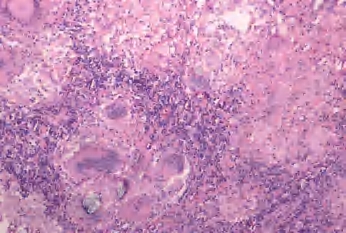

2.镜下 典型的肉芽肿中央为干酪样坏死,周边为上皮样细胞、郎罕巨细胞及炎细胞。以免疫反应为主时主要形成肉芽肿,称为增殖性结核;大部分伴有干酪样坏死,称为干酪性结核(图3-13、图3-14)。

图3-13 淋巴结结核,中心大片红染无结构物质为干酪样坏死